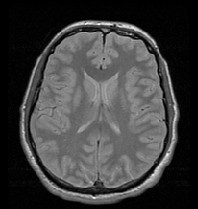

Proton density - long TR and short TE sequence, T2배제

우선 양성자 밀도 영상 - 긴 TR시간과 짧은 TE시간을 가지고 대조도가 약간 낮은 듯한 표현으로 묘사됩니다.

(영상을 많이 보는 것이 중요!!)

img.jpg

Proton density (PD)